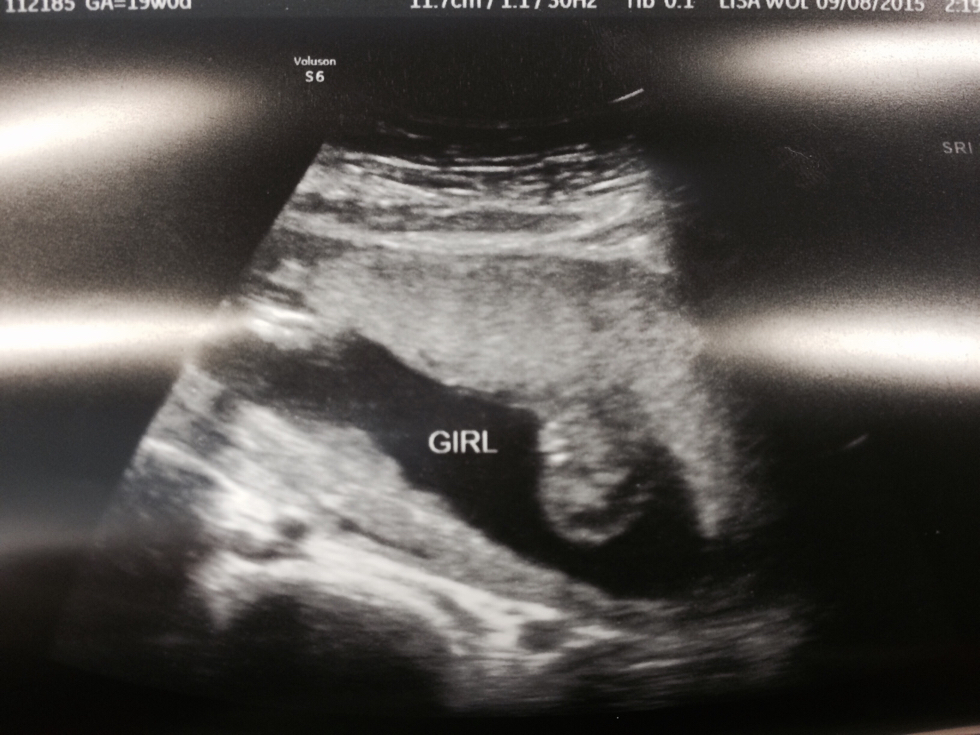

GIRL!! Jason and I are thrilled to announce we are expecting a little girl. We were 19 weeks yesterday and we had our long-awaited sonogram appointment (by far my favorite appointment!) Leading up to the visit, I had been joking with Jason that I hoped our little Peanut was cooperative in showing us his/her goodies. Sure enough, once the sonogram started, she had her little hand blocking the money shot and we had to get her moving in order to see what we were looking for. That’s my southern girl…ladylike already keeping herself covered! Jas gave me a Dum Dum sucker and the sugar shocked her into a good position. It was so crazy to see her moving around without being able to feel her. The sonographer explained that my placenta is in the front and is acting as a pillow for the baby as of now. It will likely be 2 or 3 more weeks before she is big enough for me to feel her move. I’ll just have to keep waiting!

It's a Girl!

She kept waving her hand at the camera and putting it up to her forehead...dramatic already!

The rest of the appointment went very well. I have gained a total of 4.2 pounds (that placenta in front has made my bump deceivingly big!) and my blood pressure remains low. There were no worries in regards to Mama or Baby and I always breathe a sigh of relief at a good report.

I think Jas was a little shocked seeing her on the screen and it made the whole experience a bit more real for both of us. We were so excited to start calling our family and sharing the good news. We have asked my parents for a little help in choosing the middle name for our Peanut but we expect to have a full name for our Little Lady here soon. At times, I still can’t believe we’re having a baby. And now I know I will be a mama to a little girl. I am so thrilled!